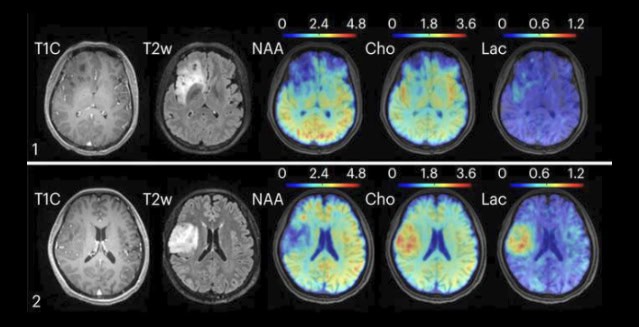

The researchers tested their MRSI technique on several populations. In healthy subjects, the researchers found and mapped varying metabolic and neurotransmitter activity across different brain regions, indicating that such activity is not universal. In patients with brain tumors, the researchers found metabolic alterations, such as elevated choline and lactate, in tumors of different grades, even when the tumors appeared identical on clinical MRI images. In subjects with multiple sclerosis, the technique detected molecular changes associated with neuroinflammatory response and reduced neuronal activity up to 70 days before changes become visible on clinical MRI images, the researchers report.